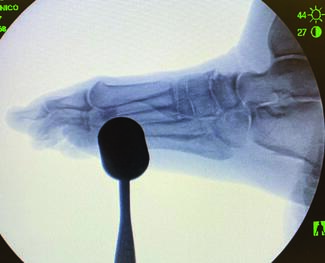

As concepts surrounding minimally invasive bunion surgery continue to evolve and improve, many have found the need to add these surgical techniques to their current skill set. This article aims to briefly review the current concepts of MIS...